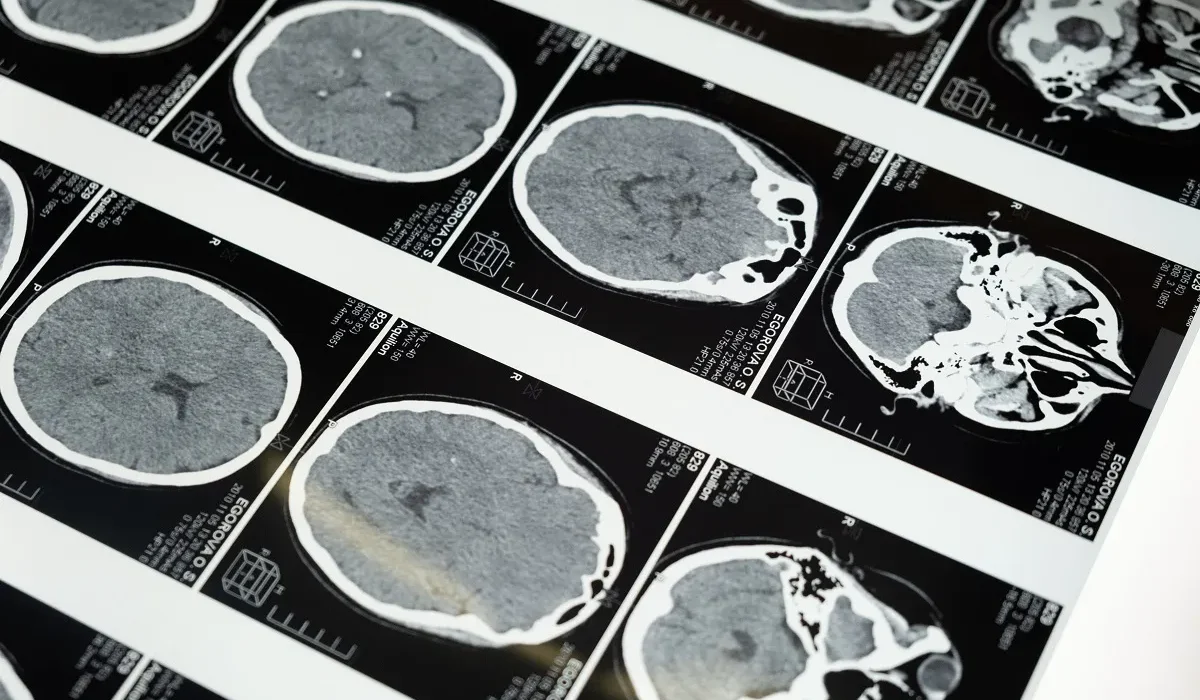

La maladie d’Alzheimer est considérée comme l’un des plus grands défis médicaux auxquels l’humanité fait face. Cette affection, qui entraîne un déclin progressif des fonctions cognitives, affecte la capacité d’une personne à reconnaître ses proches, à se souvenir des événements marquants de sa vie et, finalement, à mener une existence sereine. Depuis des années, les scientifiques s’efforcent de découvrir une cause et un traitement définitifs. Néanmoins, des allégations sérieuses surgissent, suggérant que les recherches menées au cours des deux dernières décennies reposent sur une étude utilisant des données falsifiées, selon un article récent de Science.

Ce développement constitue un véritable choc pour la communauté de recherche sur la maladie d’Alzheimer à l’échelle mondiale, sans même parler de l’impact sur les personnes affectées par cette maladie. L’étude controversée, publiée en 2006 dans la revue Nature et dirigée par Sylvain Lesné, a examiné des souris âgées souffrant de problèmes de mémoire. Elle a conclu que les déficits de mémoire chez les souris de milieu d’âge étaient liés à l’accumulation de protéines amyloïdes spécifiques, en particulier l’Aβ*56. Cette étude a donné un nouvel élan à l’idée, alors émergente, que des “oligomères toxiques”, une sous-catégorie de protéines amyloïdes, seraient à l’origine de la maladie d’Alzheimer.

Depuis sa publication, cette étude a été citée de nombreuses fois dans le domaine de la recherche sur Alzheimer, et des milliards de dollars ont été investis pour développer des traitements basés sur l’hypothèse des oligomères toxiques. Selon Science, le National Institutes of Health (NIH) a investi environ 1,6 milliard de dollars dans des projets liés à Alzheimer, mentionnant les amyloïdes, rien que pour cette année.